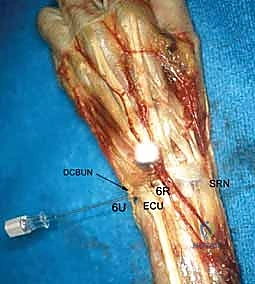

3. The 6R Portal (Radial to ECU)

- Location: On the radial side of the extensor carpi ulnaris (ECU) tendon.

- Anatomy: The ECU tendon lies within the sixth dorsal extensor compartment. Identifying the ECU is critical.

- Neurovascular Risks: Generally safe, but care must be taken to avoid the dorsal cutaneous branch of the ulnar nerve, which can course near this area.

- Function: Primarily used for instrumentation, especially when working on the ulnocarpal joint or TFCC. It allows for triangulation with the 4-5 portal.

4. The 6U Portal (Ulnar to ECU)

- Location: On the ulnar side of the extensor carpi ulnaris (ECU) tendon.

- Anatomy: Again, the ECU tendon is the key landmark.

- Neurovascular Risks: The dorsal cutaneous branch of the ulnar nerve is at increased risk here. Be mindful of its course.

- Function: Typically used as an outflow portal for irrigation fluid, but can also be used for visualization or instrumentation in specific cases.

- Function: Used in concert with the volar distal radioulnar portal to fully assess the articular cartilage of the ulnar head and sigmoid notch, and for instrumentation within the DRUJ.

Most of the complications related to use of the dorsal portals are related to injury to the sensory branches of the superficial radial nerve and the dorsal cutaneous branch of the ulnar nerve.